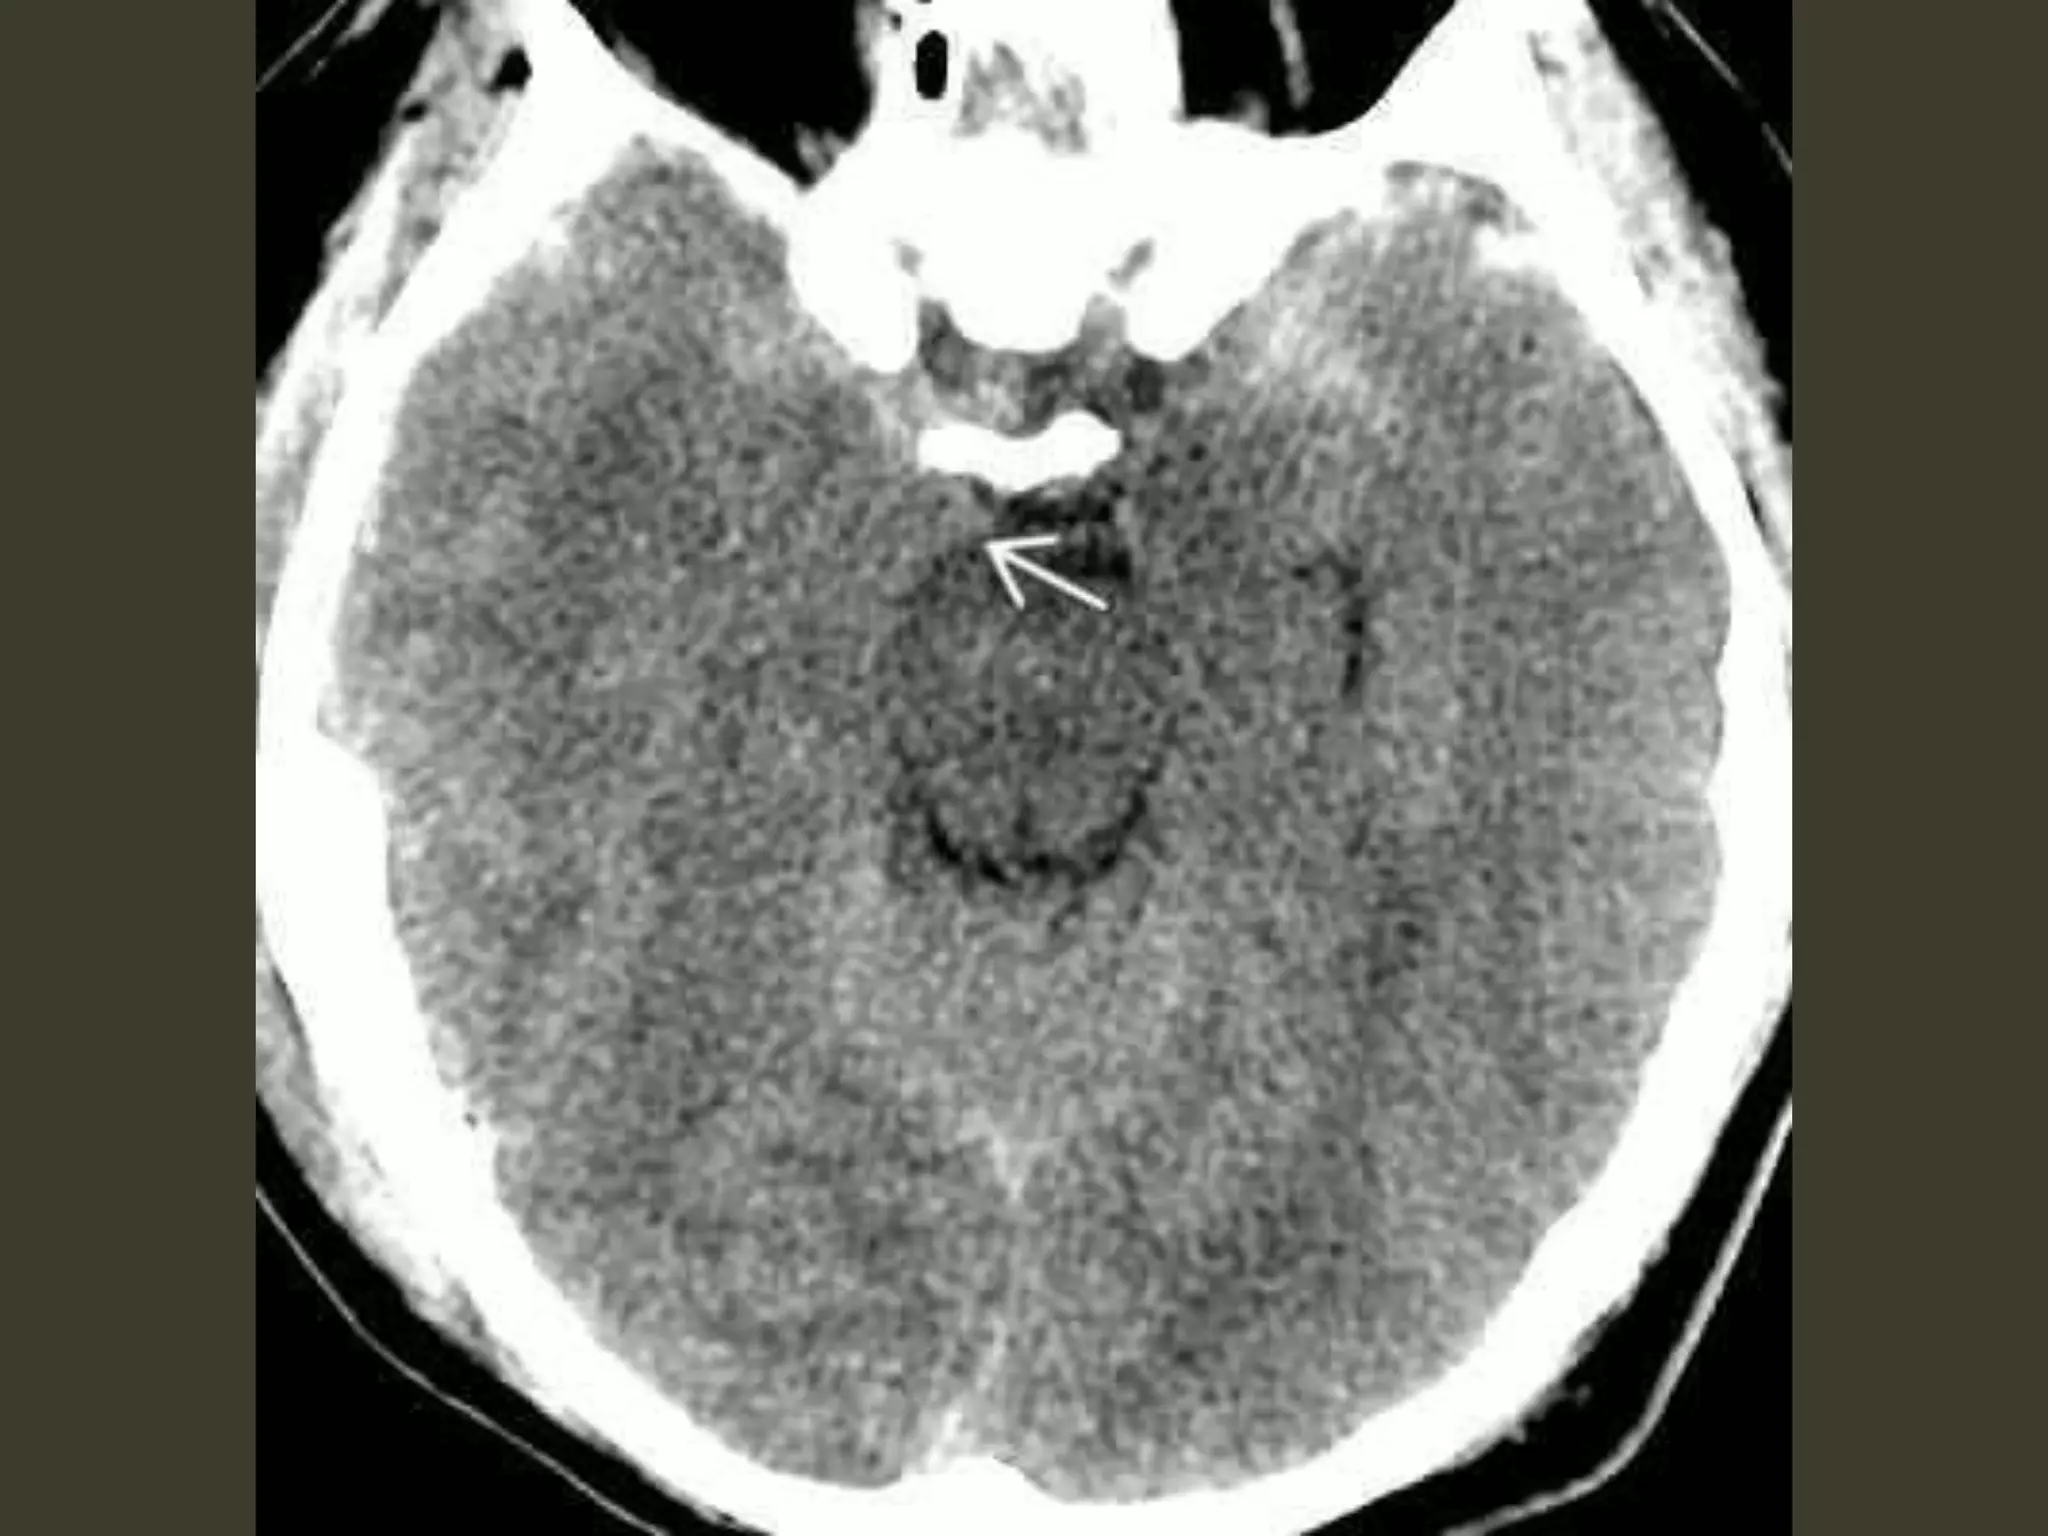

Tonsillar herniation

• The cerebellar tonsils are displaced inferiorly

and become impacted into the foramen

magnum.

Tonsillar herniation: imaging

• Diagnosing tonsillar herniation on NECT scans

may be problematic.

Cisterna magna obliteration

• In the axial plane, T2 scans show that the

tonsils are impacted into the foramen

magnum

– obliterating CSF in the cisterna magna

– displacing the medulla anteriorly

Complications

•obstructive hydrocephalus

•tonsillar necrosis